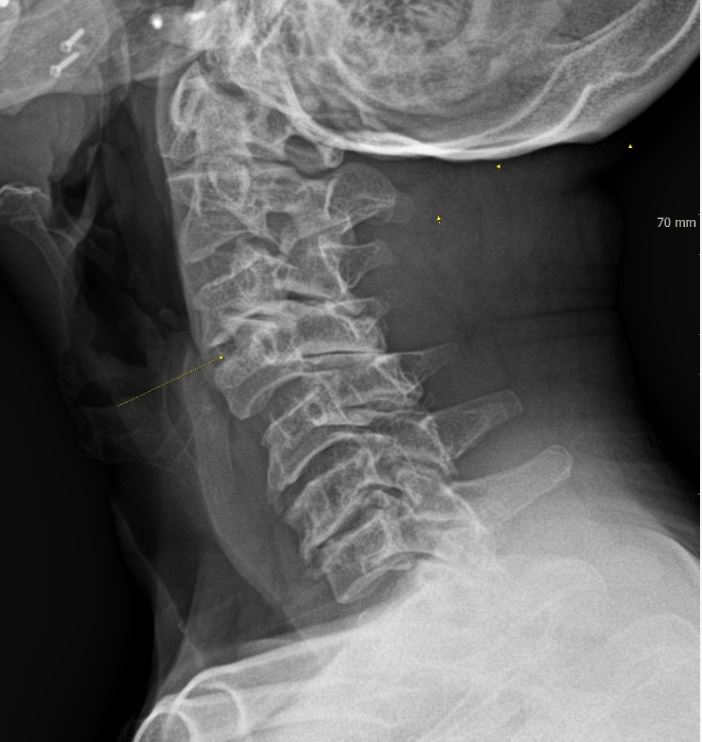

우선 목디스크란 목뼈 사이의 디스크가 손상되어 발생하는 질환을 의미합니다. 디스크는 척추뼈 사이에서 충격을 흡수하고 신경을 보호하는 역할을 하는데, 디스크가 손상되면 신경이 압박되어 통증, 저림, 마비 등의 증상이 나타납니다.

목디스크의 원인은 다양하지만, 가장 흔한 원인은 외상입니다. 외상은 교통사고, 스포츠 부상, 낙상 등 다양한 원인으로 발생할 수 있습니다. 또한, 잘못된 자세, 과도한 스트레스, 노화 등이 목디스크의 발생 위험을 높입니다.

목디스크의 증상은 다양하며 환자마다 그 증상이 다르게 나타날 수 있습니다. 가장 흔한 증상은 목의 통증입니다. 목의 통증은 목 뒤쪽, 어깨, 팔, 손까지 뻗쳐서 나타날 수 있습니다. 또한, 저림, 마비, 감각 이상, 손발의 힘 저하 등의 증상이 나타날 수 있습니다.